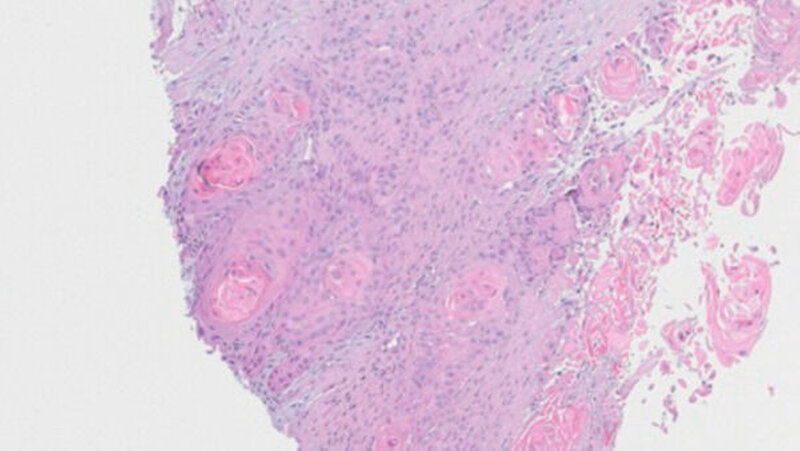

Weder das Röntgenbild noch die weitere Untersuchung mit magnetresonanztomografischer Bildgebung gaben eindeutigen Aufschluss. Daraufhin wurde eine Biopsie veranlasst, die die Verdachtsdiagnose einer Metastase des oralen Plattenepithelkarzinoms histologisch bestätigte.

Plattenepithelkarzinome sind von den Epithelien der Haut und der Schleimhäute ausgehende bösartige Tumoren, die häufig metastasieren über die abführenden Lymphgefäße in regionale oder weiter entfernt liegende Lymphknoten. Sie gelten als zweithäufigste bösartige Hauttumoren. Man geht von rund 70.000 Neuerkrankungen pro Jahr aus. Eine Streuung dieses Karzinoms über den Blutweg ist sehr selten, aber kann - wie in diesem Fall - sogar vom Mundboden bis in den Oberarm reichen.